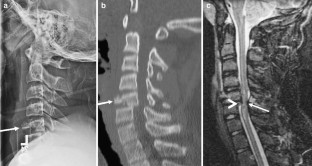

Fig. 4